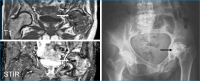

Knocheninfarkt

Abbildung 1: MRI T1 und STIR untere Extremitäten: Knocheninfarkte in den Femura beiderseits und in der linken Tibia (Pfeile).